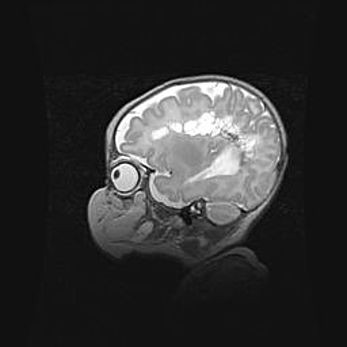

Множественные кисты обоих полушарий головного мозга, наибольшая из них в правой затылочной области. Ассиметричная атрофическая гидроцефалия.

Возраст: 7 месяцев

Вес: 5660 г

Пол: мужской

Окружность головы: 41,5 см

Срок гестации: 28-29 недель

Кисты головного мозга развиваются в результате многоочаговых некрозов вещества мозга и возникают вследствие перенесенной перинатальной инфекции, менингитов, энцефалитов, асфиксии, родовой травмы, расстройств мозгового кровообращения различного генеза. Образованию кист в веществе головного мозга плодов и новорожденных способствуют такие факторы, как высокое содержание в нем воды, недостаточная (или отсутствие) миелинизация и слабая астроглиальная реакция на повреждение.

Кисты могут сочетаться с гидроцефалией и другими поражениями головного мозга.